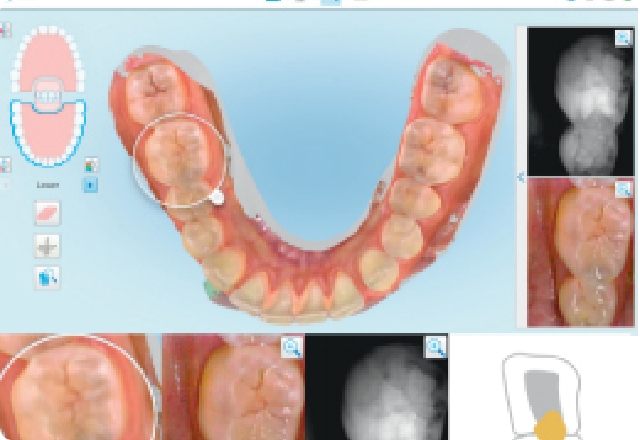

より精密で安心な矯正治療を

ご提供

より精密な矯正治療のために高精度歯型3Dスキャン「iTero element 5D」を導入しております。

口腔内の状態を3Dデータとして精密に取り込むことができるため、シリコンでは再現できなかった細かな凹凸まで再現することが可能です。

これにより、たくさんの患者様が安心して治療頂ける歯科矯正をご提供いたします。

STEP033Dシュミレーション

(3Dデジタル分析)

治療開始から完了までの歯の移動を、クリンチェックソフトウェア(3Dシミュレーションソフト)を用いてシミュレーションします。最終的に患者様の歯並びがどのようになるのか、映像を見ながら患者さまにご説明させていただきます。